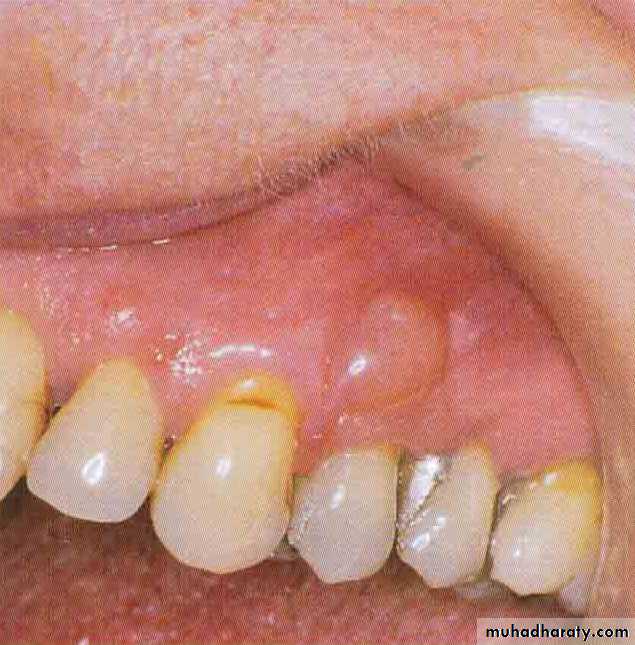

Gingival cyst of adults

Exceedingly rare.Usually form after the age of approximately 40 years.

They form dome shape swelling less than 1 cm in diameter and some time erode the underlying bone.

They are lined by very thin, flat stratified sequamous epithelium.

May contain fluid or layers of keratin.

Unlikely to recur after enucleation.